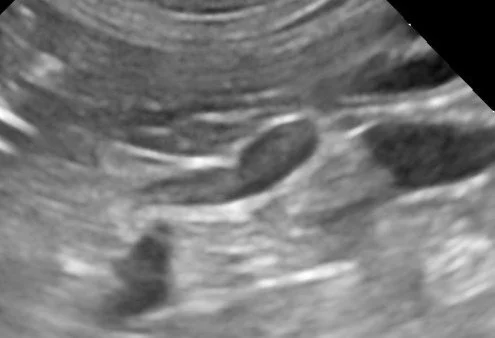

Ultrasound can, of course, be of great use in confirming pregnancy and fetus viability.